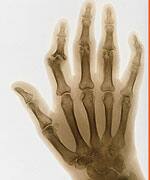

In recent years, adults seeking relief from the crippling pain of arthritis have had to choose between expensive, potentially dangerous pain-relief drugs and safer but slower-acting supplements that support joint health. While supplements such as glucosamine and chondroitin sulfate have been repeatedly shown to improve both arthritis symptoms and joint functionality, it may take weeks or even months for the benefits to be felt—offering little relief in the meantime for those with severe, debilitating joint pain. Fortunately, several new compounds have been identified that work quickly to relieve pain and promote rapid healing, thus bridging the gap between the onset of discomfort and the beginning of relief. These new-generation compounds not only offer faster-acting pain relief, but also work over time—either alone or in combination with traditional joint-health supplements—to provide comprehensive, broad-spectrum support for joint repair and tissue regeneration. New Weapons for Fighting Joint PainHealth-conscious adults who are interested in maintaining healthy joints have long relied on nutritional supplements such as glucosamine chondroitin sulfate, and methyl-sulfonylmethane (MSM). While years of rigorous scientific study attest to the effectiveness of these supplements in relieving pain and supporting long-term joint health, one drawback has been compliance; high doses are required to obtain the maximum benefit. Another drawback is their onset of action.Put simply, these traditional supplements take time to work, with studies suggesting that it may take two weeks or often even longer longer to fully experience their effects.1-8 Understandably, this delay in apparent relief may cause some patients to abandon therapy too soon. Patience is a virtue, but when pain strikes, it is only natural to seek immediate relief. The good news is, scientists have made great progress in developing joint-health supplements with a more rapid onset of action. These remarkable compounds—which naturally nourish joint fluids and tissues, while improving joint pain and functionality in just hours or days—represent impressive new weapons in the pain-relief arsenal. They include:

Keratin: Antioxidant Protection and Support for Joint RepairHuman joints are exceedingly vulnerable to the effects of aging,10 due to both everyday wear and tear and the ubiquitous presence of oxidative stressors. Scientists have now formulated a novel compound composed of keratin to counteract the various forces that degrade joint health over time. Keratin benefits joint health by:

Found in much of the body’s connective tissue (including skin, hair, and teeth), keratin is actually a class of fundamental proteins containing an exceptionally high content of the amino acid cysteine. Cysteine is a rich source of sulfur molecules, which make up an important constituent of joint tissue. When sulfur molecules bond to one another, they form an extraordinarily strong link. These “cysteine bridges” provide much of keratin’s structural rigidity. Such rigidity is a highly desirable trait in weight-bearing joints, which require both flexibility and resilience in order to function as effective shock absorbers.

Sulfur plays an important, multifaceted role in healthy joint tissue. Joints are made up in part of biological polymers, or compounds consisting of smaller, identical molecules linked together. Sulfation is the incorporation of sulfur molecules in these polymers, a process that occurs naturally when joints are healthy. Proteoglycans, which are protein-sugar polymers, gain much of their flexibility and crush resistance from these sulfur-to-sulfur bonds. Diseased joints, by contrast, are characterized by impaired sulfur metabolism.11-16 When joints are no longer able to incorporate sulfur efficiently, their structure deteriorates, leading to pain and stiffness. By supplying a source of sulfur-rich cysteine, keratin may contribute to the synthesis of proteoglycans in the cartilage responsible for cushioning joints. In addition to supporting healthy joint structure, keratin offers important antioxidant support to joint tissues. It not only acts as an antioxidant itself, but also supplies cysteine to the joints, which works as an intracellular antioxidant to fight damaging reactive oxygen species. Furthermore, the body uses cysteine derived from keratin to help manufacture glutathione, one of its most important and multifunctional antioxidant molecules. Glutathione plays a central role in detoxification reactions in the liver. It is also an essential component of glutathione peroxidase, an enzyme that provides direct antioxidant protection for cells and is especially important for healthy joint tissues.17,18 Keratin thus supports joint health via two critical mechanisms: by stimulating the synthesis of essential joint-supporting proteoglycans, and by promoting the production of joint-protective antioxidants in the body.19 In an effort to capture these beneficial effects, scientists in New Zealand have formulated Cynatine FLX ™, a soluble form of the keratin protein that is bioactive in the body. | ||||